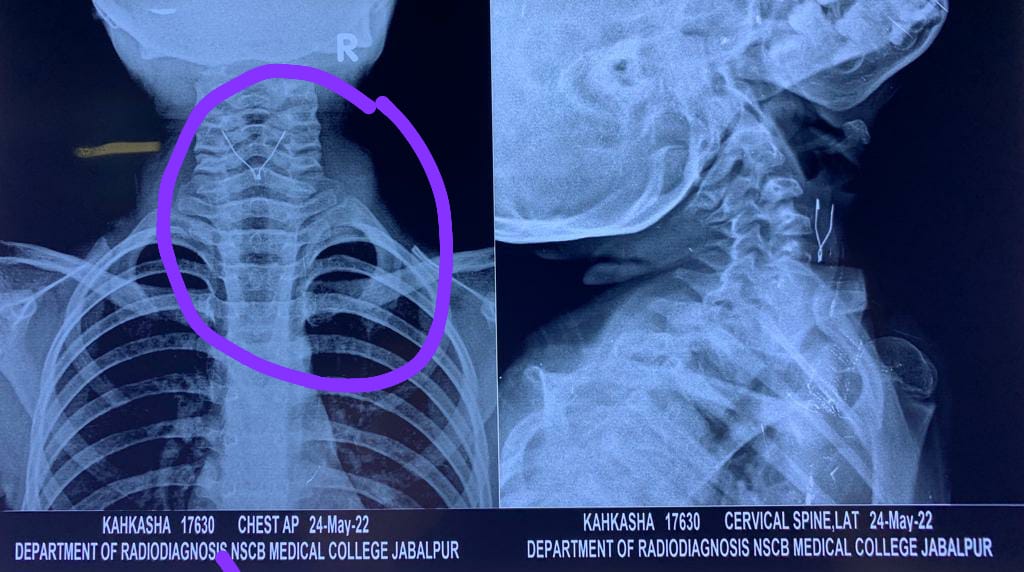

ईएनटी विभाग की हेड डॉक्टर कविता सचदेवा ने बताया कि मंगलवार की शाम न्यू आंनद नगर अधारताल निवासी शेख मोहम्मद अपनी 6 साल की बच्ची सहकशा को लेकर पहुंचे और बताया कि उसने खेल-खेल में एलईडी पेन खा लिया है। इसकी वजह से बच्ची को गले में दर्द हो रहा है और वो कुछ बोल नहीं पा रही है। ईएनटी विभाग टीम ने बगैर देर किए हुए बच्ची का ट्रीटमेंट शुरू किया और आज मंगलवार को बच्ची का ऑपरेशन कर एलईडी पेन को बाहर निकाला गया। डॉक्टर कविता सचदेवा ने बताया कि सफल ऑपरेशन के बाद बच्ची पूरी तरह से स्वस्थ्य है।